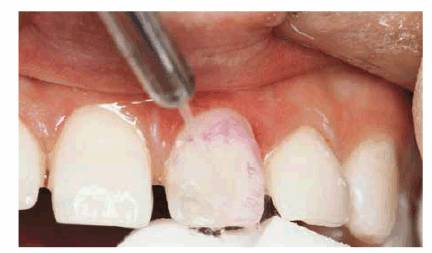

TREATMENT: To maximize longevity and esthetics, porcelain laminates were

chosen as the most conservative treatment. Figure 23-14B shows the previously bonded left central

incisor coated with dentin-disclosing solution to determine how much enamel was

left. The tooth is washed, leaving red dye to indicate dentin areas (see Figure 23-14C). Figure 23-14D shows the left central incisor laminate being bonded

Figure 23-14B: Dentin disclosing solution is applied to determine how much enamel remained on this previously bonded left central incisor.

Figure 23-14C: Red dye indicates the areas of dentin.